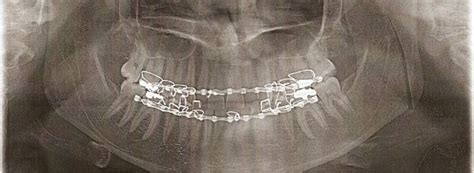

Weight Loss Jaw Wiring: Benefits, Selfcare, Risks & Cost